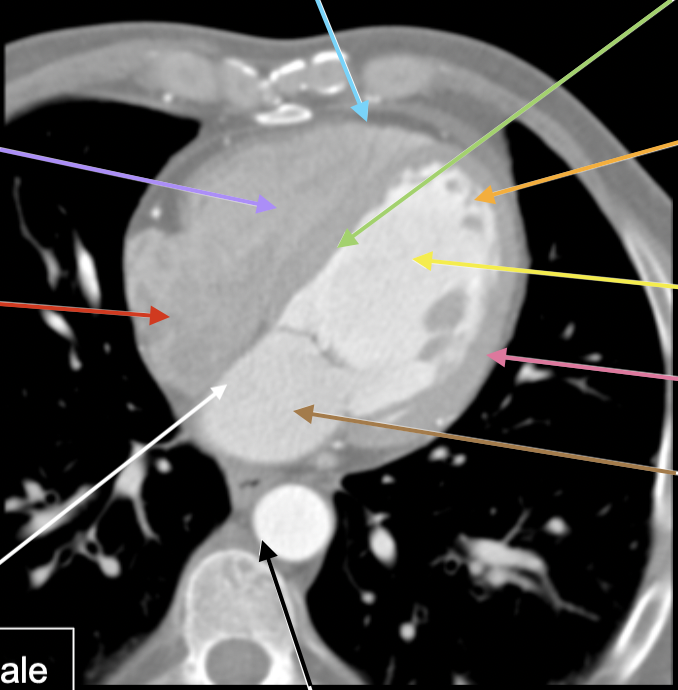

apex cordis

röd

85

New cards

trabeculae carneae

svart

86

atrium sinistrum

lila

87

aorta descendens

88

septum interatriale

vit

89

atrium dx

90

ventriculus dx

91

cavum pericardi

blå

92

septum interventriculare

grön

93

orange

94

ventriculus sin

gul

95

myocardium

rosa

96

atrium sin

brun

97

valva aortae

98

vv pulmonalis dx

99

vv pulmonalis sin

100

esophagus